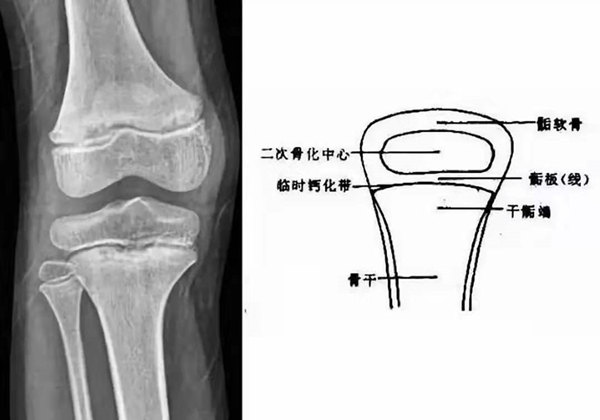

我們都知道,人體的高矮是由骨骼的生長發(fā)育決定的,特別是下肢長骨。長骨呈長管狀,在長骨的兩端有一種專管骨骼生長的骺軟骨,它與干骺端之間有一盤狀軟骨結構稱為骺板(線),在幼兒的X光片上表現(xiàn)為一條較寬的透光帶。 (見下圖)

未成年時隨著年齡的增加骺軟骨端不斷骨化,骨骼就不斷增長。當骨骺線完全閉合時骨骼就停止生長,個子也就不再增長了。一般骨骺端完全閉合的年齡是18~20歲左右。